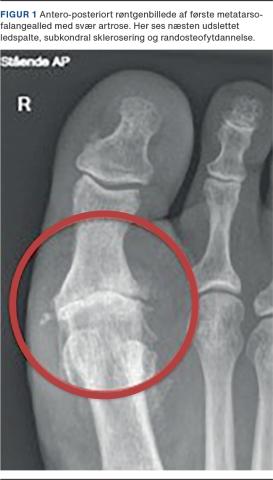

Til vurdering af første MTP-led anvendes røntgenbilleder, minimum i to projektioner (antero-posterior (Figur 1) og sideoptagelser (Figur 2)) med patienten stående med fuld vægt på foden. Røntgenbillederne, hvor der er belastning på foden, giver også et overblik over andre deformiteter, f.eks. hallux valgus, hammertå, instabilitet eller degeneration i fodens øvrige led.

De typiske røntgenfund er dorsal osteofytdannelse på caput af første metatars, afsmalnet ledspalte i første MTP-led, affladet caput af første metatars, subkondrale cyster, subkondral sklerosering og evt. ledmus. Der er stor variation i, hvilke og hvor mange af de radiologiske fund der forekommer hos den enkelte patient [4].